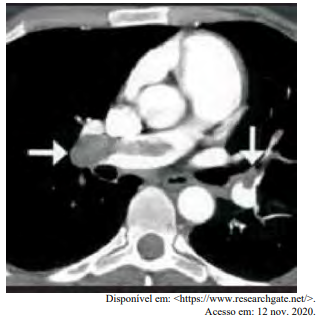

Certa idosa de 70 anos de idade é levada ao consultório médico por familiares, com relato de dor no peito há oito horas. Quanto a comorbidades, ela apresenta hipertensão arterial sistêmica e insuficiência cardíaca. Estava em casa assistindo à televisão quando sentiu uma dor súbita no peito, de moderada intensidade, que piora com a inspiração profunda, irradiando para o dorso, em queimação e associada a palpitações e a falta de ar importante, mesmo em repouso. Nega náuseas e sudorese. Não melhora após tomar dipirona. A dor continua da mesma forma, mas o que levou os familiares a procurarem atendimento foi a piora da falta de ar. Faz uso de losartana, atenolol, espironolactona, AAS e sinvastatina. Nega etilismo e informa que tinha o hábito de tabagismo, mas parou há mais de 10 anos. Tem histórico anterior de cirurgia de artroplastia de quadril há mais de um ano. Tem ficado muito tempo em repouso, assistindo à TV, principalmente depois da pandemia de Covid-19. Ao exame físico, constatam-se PA = 89 mmHg x 59 mmHg, FC = 125 bpm, FR = 27 ipm e SatO2 = 89% em ar ambiente. A paciente está afebril, em estado geral regular, lúcida, orientada e comunicativa. As auscultas pulmonar e cardíaca mostram-se sem alterações. Observam-se abdome inocente, membros inferiores com cacifo + discreto e simétrico, panturrilhas livres e pulsos preservados. A paciente realiza o eletrocardiograma e a tomografia de tórax, conforme representado nas imagens a seguir.

Com base nesse caso clínico, nos exames representados nas imagens e nos conhecimentos médicos correlatos, julgue o item a seguir.

A tomografia apresenta uma área compatível com infarto miocárdico transmural, que é compatível com infarto agudo do miocárdio silencioso.